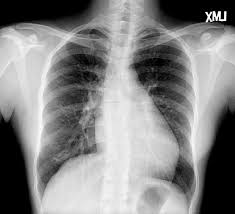

Thorax X Ray Showing Cardiomegaly With A Cardiothoracic Index Of 0 55 Download Scientific Diagram